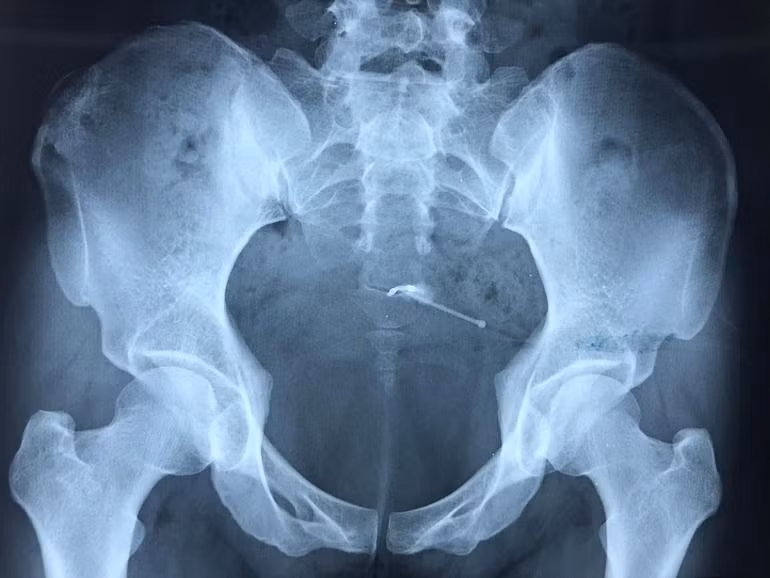

Kết quả siêu âm phát hiện sỏi bàng quang kích thước # 9x17mm, các bác sĩ hội chẩn quyết định nội soi bàng quang.

Trong quá trình phẫu thuật nội soi bàng quang, các bác sĩ phát hiện có dị vật xuyên thành bàng quang tạo thành một khối đường kính khoảng 5mm, nhưng do dị vật bám chắc vào thành bàng quang nên không thể lấy qua nội soi.

Sau đó, các bác sĩ tiến hành chụp cắt lớp vi tính, kết quả ghi nhận: Dụng cụ tránh thai lạc chỗ vùng ngoài tử cung cạnh thành trên, xuyên thành bàng quang, kích thước #3 cm.

Các bác sĩ hội chẩn quyết định phẫu thuật lấy vòng tránh thai bị lạc chỗ. Sau khoảng 1 giờ phẫu thuật, các bác sĩ đã lấy ra vòng tránh thai dài khảng 4cm được bao chặt bởi các cơ xung quanh. Hiện bệnh nhân ổn định, không sốt, vết mổ khô.